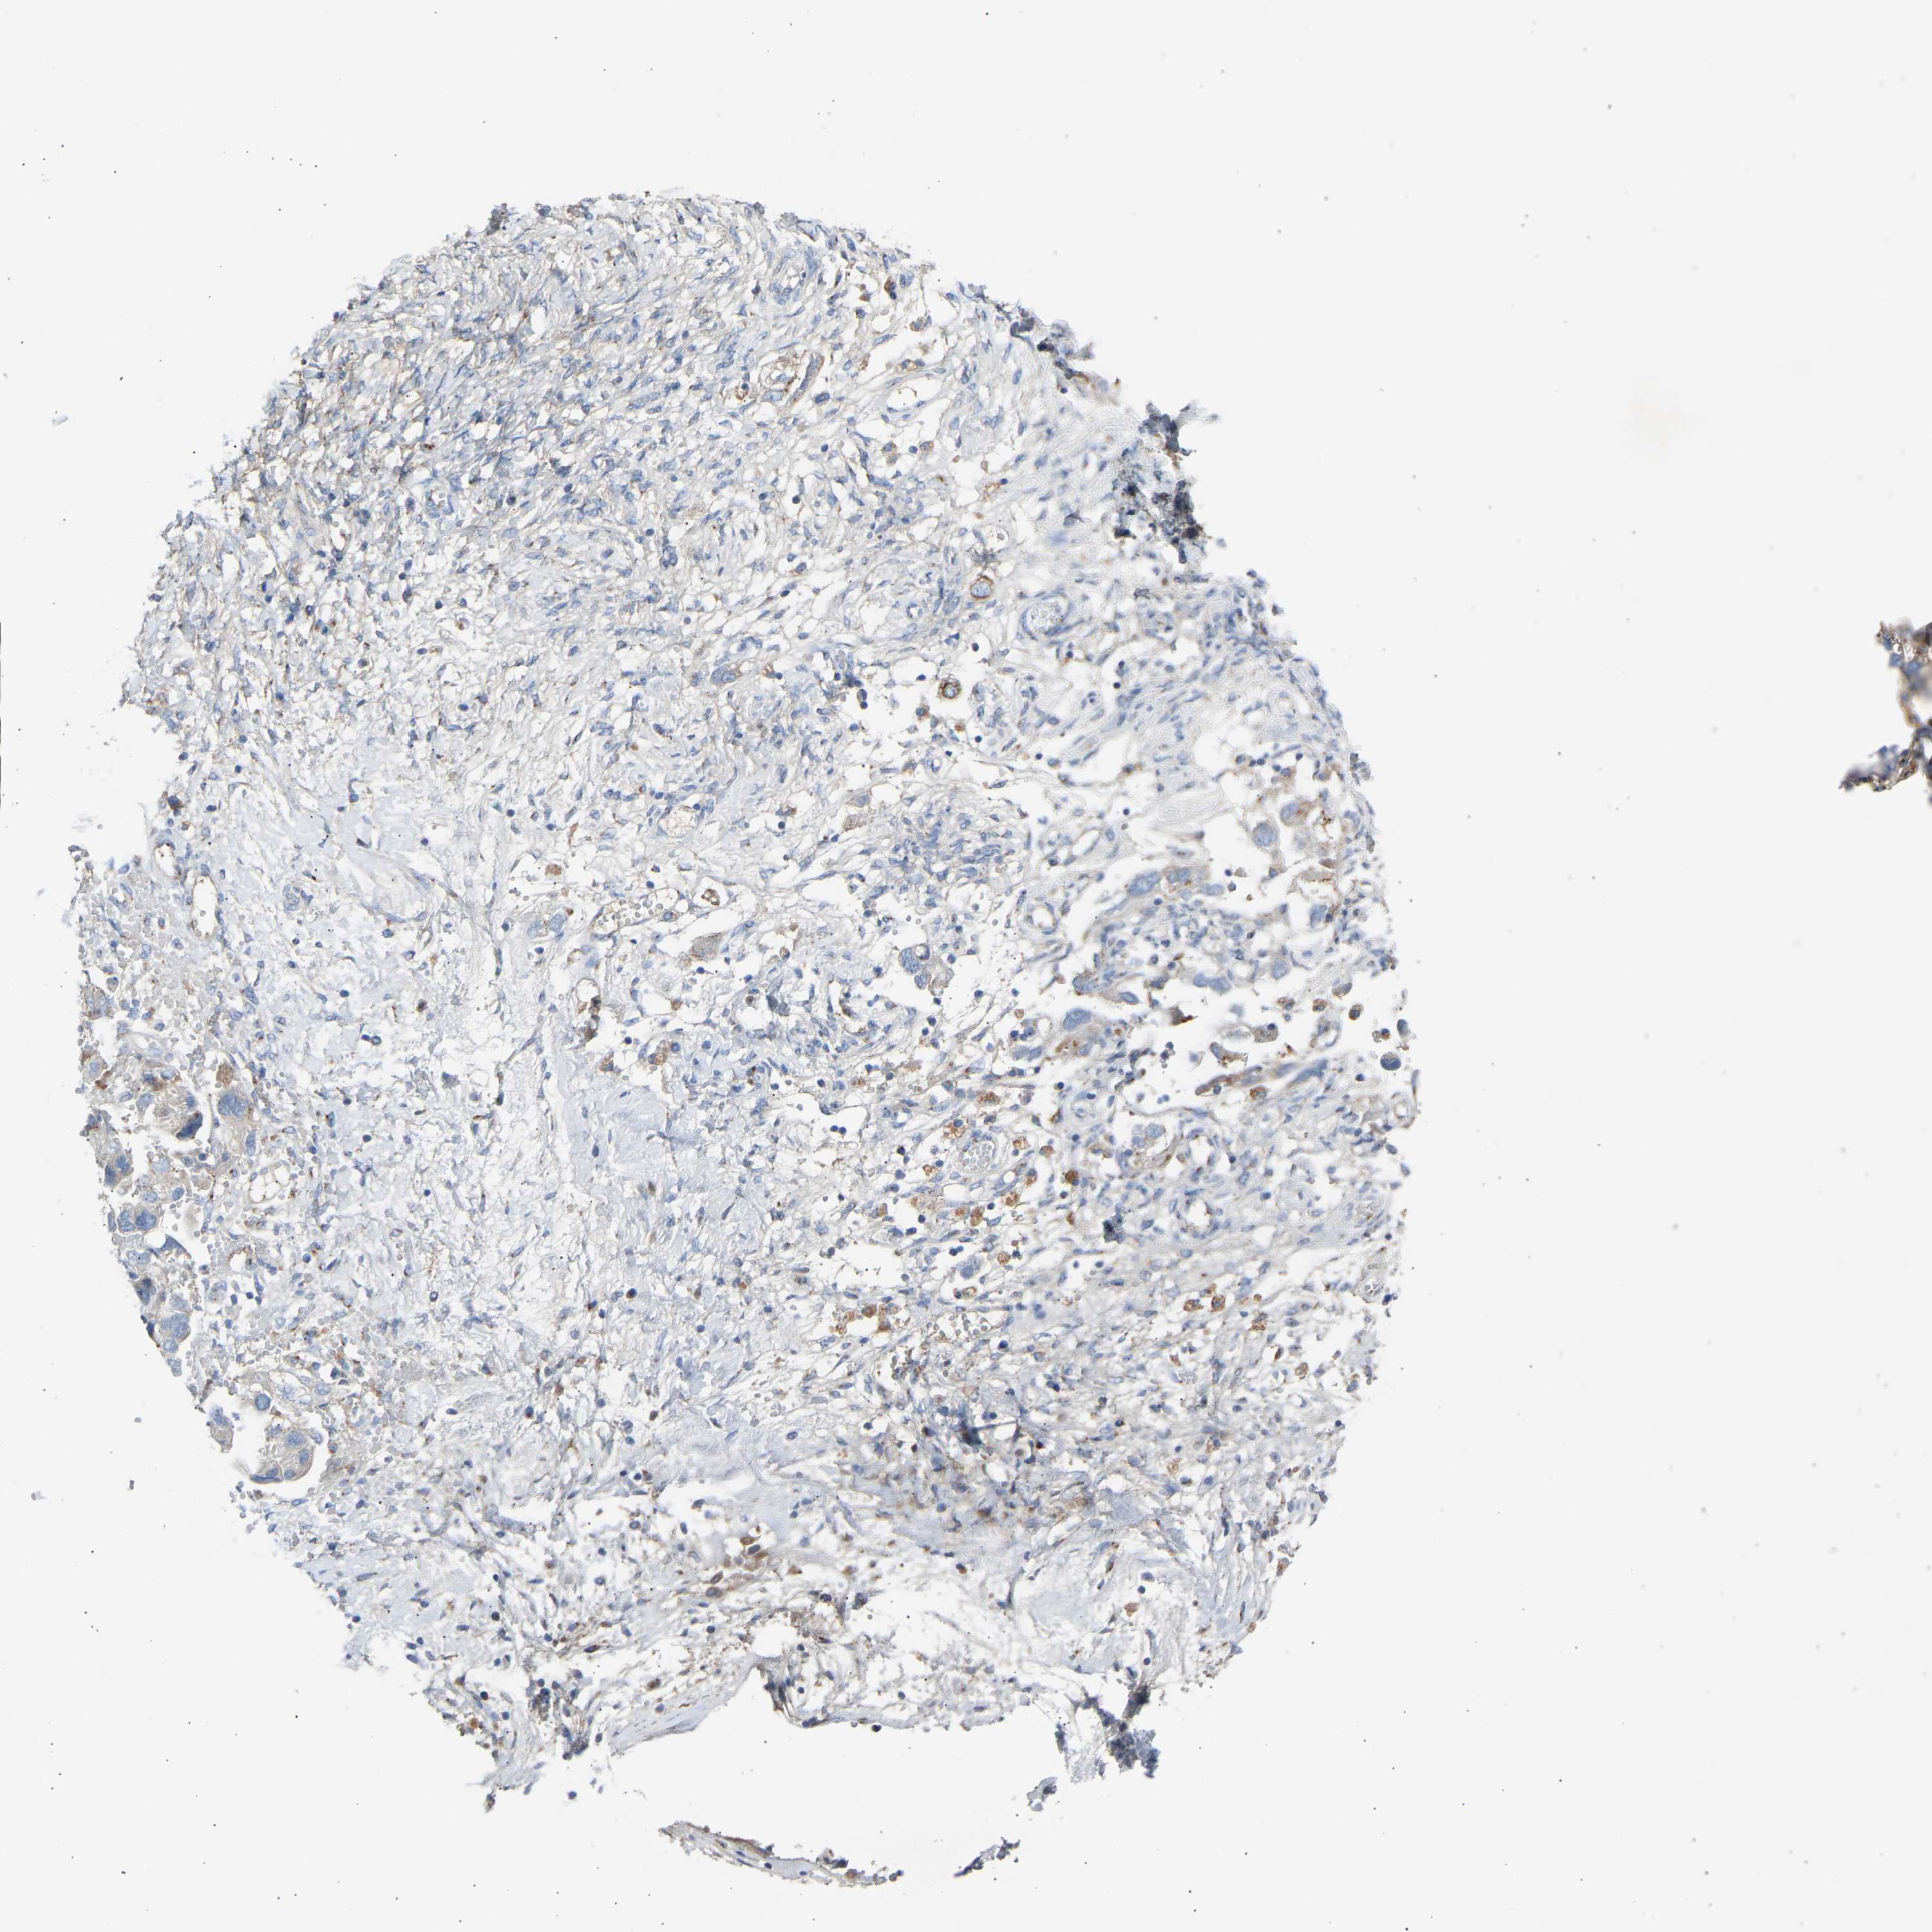

OVARIAN CANCER - Protein expressioni

A mouse-over function shows sample information and annotation data. Click on an image to view it in a full screen mode. Samples can be filtered based on level of antibody staining by selecting one or several of the following categories: high, medium, low and not detected. The assay and annotation is described here.

Note that samples used for immunohistochemistry by the Human Protein Atlas do not correspond to samples in the TCGA dataset.

Antibody stainingi

Antibody staining in the annotated cell types in the current human tissue is reported as not detected, low, medium, or high, based on conventional immunohistochemistry profiling in selected tissues. This score is based on the combination of the staining intensity and fraction of stained cells.

Each image is clickable and will lead to virtual microscopy that enables deeper exploration of all samples and also displays staining intensity scores, fraction scores and subcellular localization as well as patient and tissue information for each sample.

Antibody HPA020060

Cystadenocarcinoma, serous, NOS

Carcinoma, endometroid

Cystadenocarcinoma, mucinous, NOS

Carcinoma, NOS